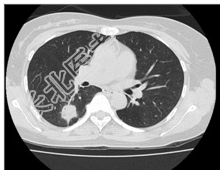

- [材料题] 患者,女性,47岁,体检发现右肺结节。查体:双肺呼吸音清,未闻及干湿性啰音。心脏体查无异常。行胸部CT平扫及增强。

- 简答题1、患者的诊断及依据是什么?

- 简答题2、鉴别诊断有哪些?